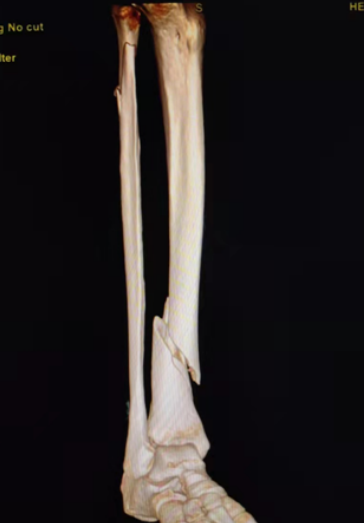

典型病例:女性,56歲,術前CT提示脛骨中下段骨折,移位明顯。

術后正側位片提示骨折達解剖復位,力線恢復正常。